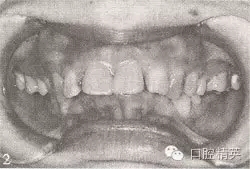

参见图9-33 双侧后牙锁颌矫治前后

A.双侧后牙锁颌矫治前